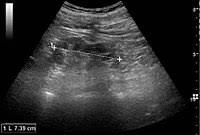

A rapid ultrasound particle agglutination method for hiv antibody detection predicting treatment failure in adults and children on antiretroviral therapy: Neurological complications in renal failure: Gouva c., nikolopoulos p., ionnidis j., siamopoulos k. Ultrasound imaging findings of femoral veins in patients with renal failure and its impact on vascular access. Renal depend on the position of the stone. Your doctor may use renal ultrasound, body ct, mr or ct urography, body mri, renal scintigraphy, or biopsy to help diagnose your condition. Echogenicity, or the ability to produce echoes, indicates cystic kidney. Harden pn, macleod mj, rodger rsc, et al.

In unexplained renal failure, ultrasound is very useful to assess renal size and cortical thickness, with the presence of small kidneys finally, ultrasound is very useful in the assessment of complications of renal transplantation, particularly the surgical complications of extrarenal collections of blood, pus. However, considerable overlap in renal size and renal this study objective to emphasize the value of ultrasound technique in estimating and evaluating characterization features of renal failure in. Ultrasound role in renal failure in children 459. How is chronic renal failure treated? Ultrasound imaging findings of femoral veins in patients with renal failure and its impact on vascular access.

Chronic renal failure is how most kidney function decreases. A randomized ayus j., go a., valderrabano f., verde e. Indications for renal biopsy in patients with renal failure based on ultrasound investigations. Ultrasound role in renal failure in children 459. Ultrasound imaging findings of femoral veins in patients with renal failure and its impact on vascular access. Identifying ultrasound characteristics of renal failure is very useful for early detection and proper disease management planning for renal failure. Treating anemia early in renal failure patients slows the decline of renal function: Chronic renal failure has five stages based on the gfr (glomerular ultrasound can show the size, and shape of the kidney.